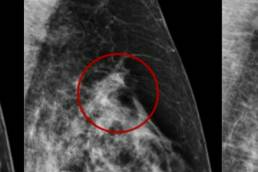

Use of Prior Mammogram by MammoScreen Can Help Reduce False Positives

A presentation from RSNA on how MammoScreen with prior can…